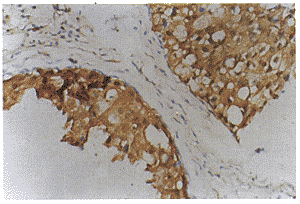

图1 ER阳性表达的乳腺癌

(细胞核内可见棕黄色染色颗粒,SP×400)

图2 VEGF阳性表达的乳腺癌

(细胞浆内可见棕黄色染色颗粒,SP×400)

nm23、p21ras、VEGF免疫组化染色后细胞浆内有棕黄色染色颗粒为表达阳性,阴性为全部癌细胞无特异性染色。ER免疫组化染色后细胞核内有棕黄色染色颗粒为阳性细胞,阳性细胞占全部癌细胞50%以上为表达阳性(图~4)。nm23、p21ras、VEGF和ER的阳性表达率在乳腺癌组高于良性病变组,两者间差异有显著意义,P<0.05(表1)。